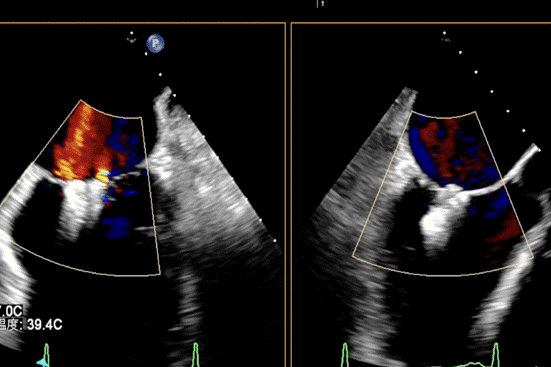

患者全麻成功后,经右股静脉建立路径,穿刺房间隔,瓣膜夹通过输送系统送入左心房,顺利到达病变二尖瓣区域。在经食道超声和DSA的辅助下,通过反复评估二尖瓣返流位置、抓捕位置、返流程度,最终在A2P2位置植入一枚DragonFly™夹子。手术操作时长48分钟,透视时间总计为5分钟,术后患者无不适感,整个手术流畅完美,患者返流程度降至微量。

检查,诊断为慢性心脏功能不全急性加重,缺血性心肌病,二尖瓣关闭不全(重度),心功能Ⅱ级,术前经胸超声检查提示二尖瓣关闭不全(A1、A2区及P2区)重度,二尖瓣返流束宽度3.0cm,有效返流口面积(EROA)=0.52cm²,二尖瓣返流面积14.3cm²,左室射血分数(LVEF)为36%。

患者全麻成功后,经右股静脉建立路径,穿刺房间隔,瓣膜夹通过输送系统送入左心房,顺利到达病变二尖瓣区域。在经食道超声和DSA的辅助下,通过反复评估二尖瓣返流位置、抓捕位置、返流程度,最终决定在A2P2位置植入俩枚DragonFly™夹子,显著改善了患者的返流情况。手术操作时长60分钟,透视时间总计为15分钟。术后患者无不适感,整个手术流畅完美,患者返流程度从重度降至轻度。